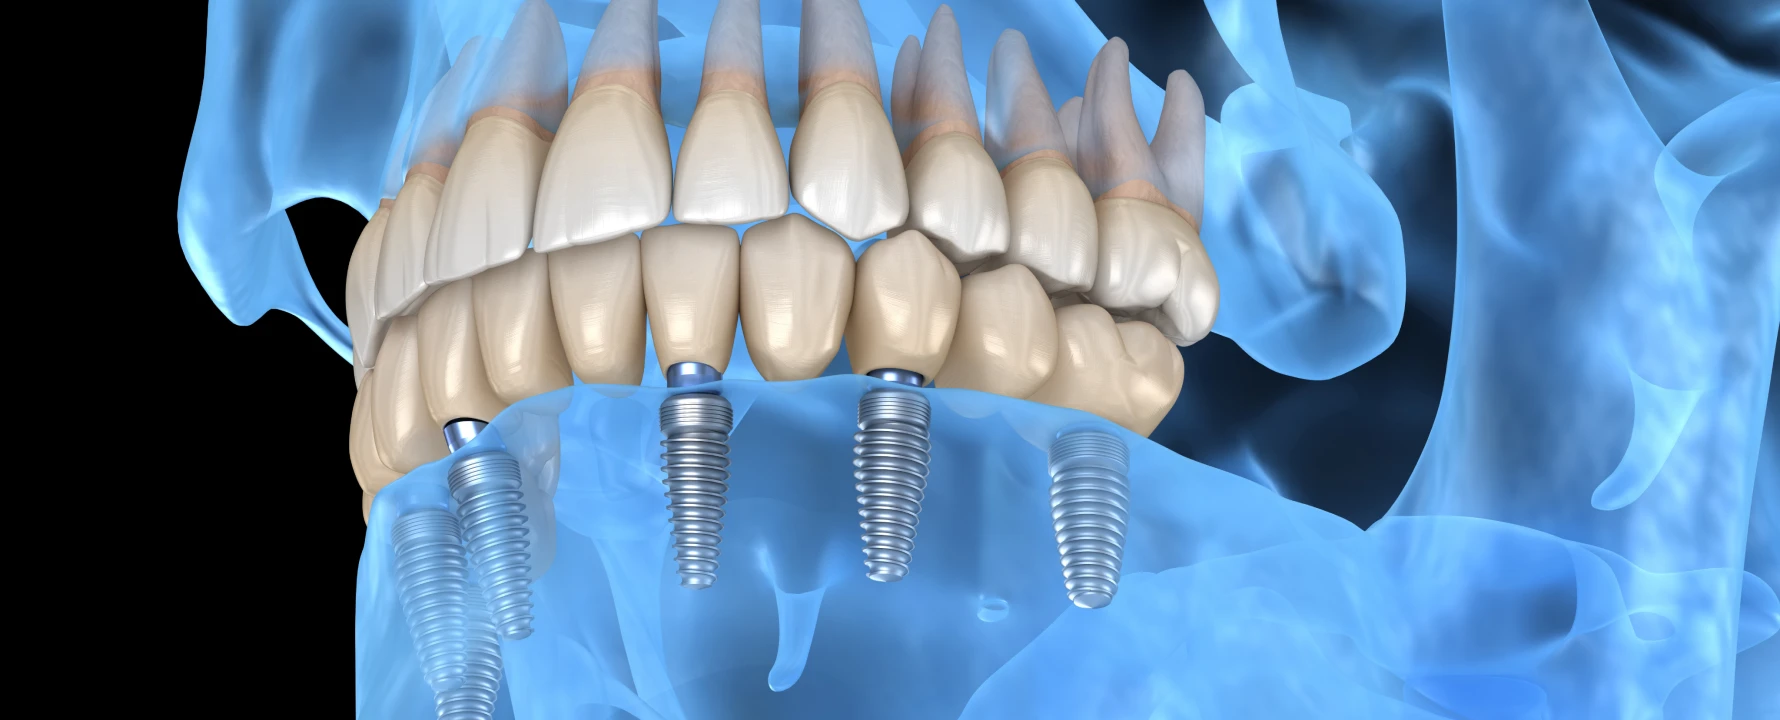

Le terme All-on-6 signifie « tout sur six ». Il décrit une réhabilitation implanto-portée où une prothèse fixe complète repose sur six implants. Les implants, insérés dans l’os maxillaire ou mandibulaire, agissent comme des racines artificielles. Ils soutiennent une arcade complète de dents artificielles conçues pour restituer une fonction masticatoire et un sourire esthétiques.

La chirurgie guidée par ordinateur est toujours utilisée. Elle repose sur un modèle 3D de la mâchoire, permettant de définir l’emplacement exact des implants. Des guides chirurgicaux sont fabriqués pour guider les gestes du praticien.

Sous anesthésie locale, six implants en titane sont posés. Leur répartition est optimisée : quatre implants dans la zone antérieure et deux implants postérieurs pour équilibrer les forces.

Les implants sont en titane, matériau biocompatible qui s’intègre parfaitement à l’os.